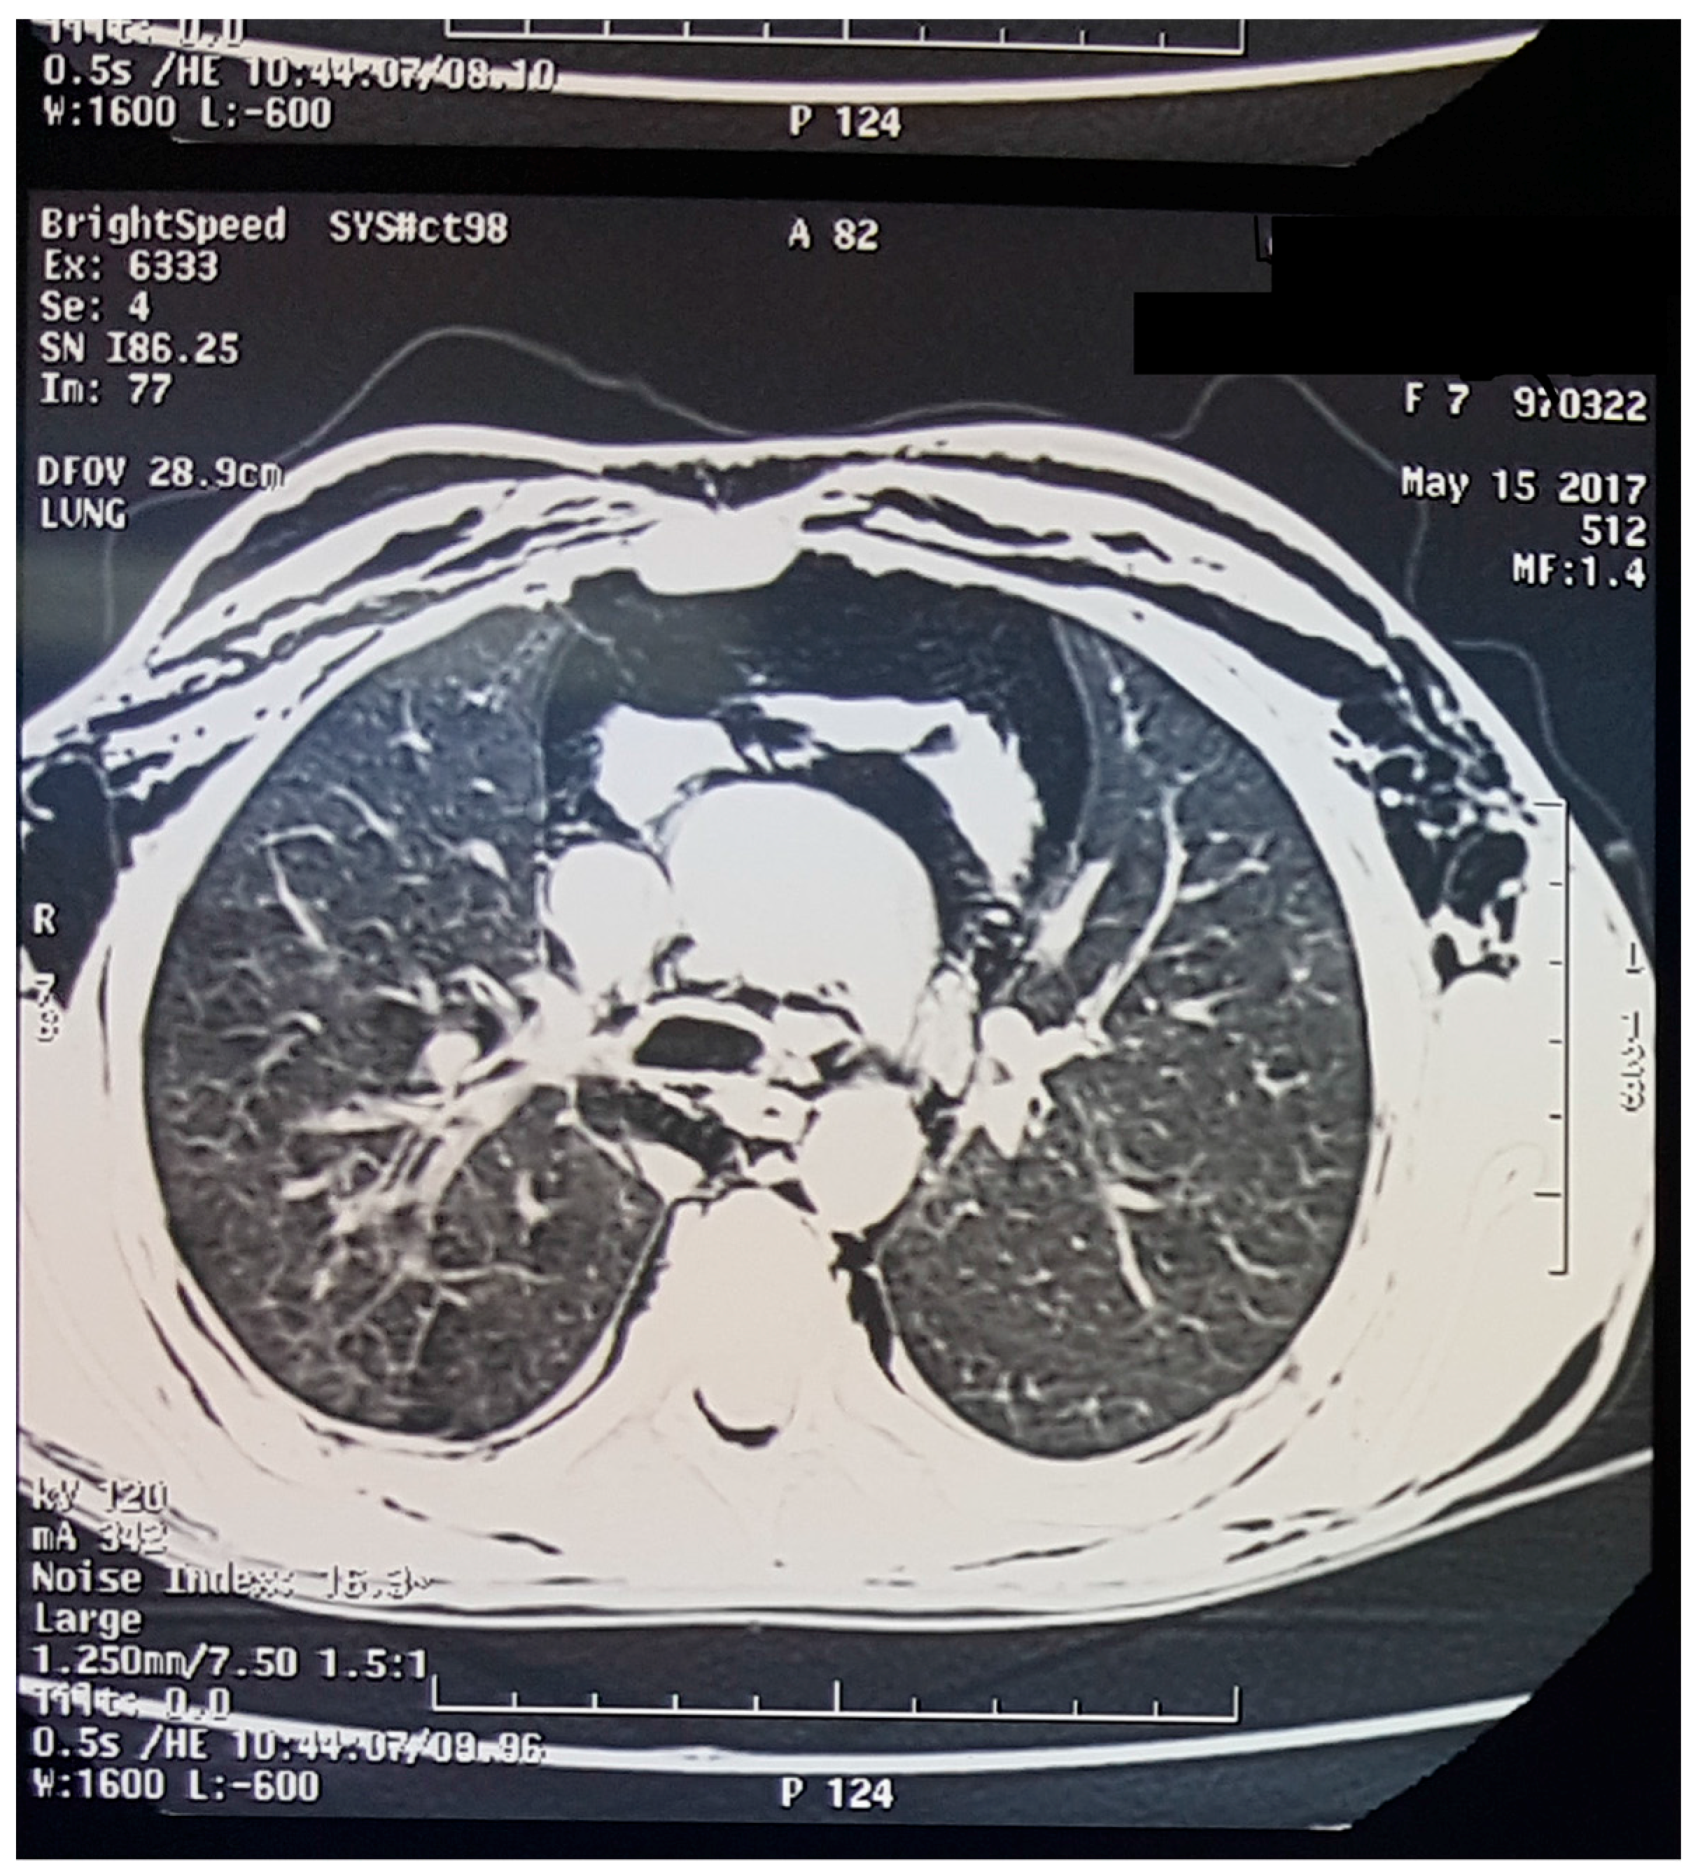

2. Case Presentation